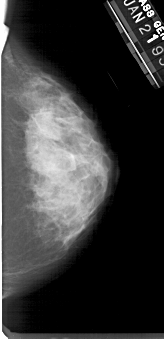

A_1353_1.RIGHT_CC

RIGHT_CC LINES 5071 PIXELS_PER_LINE 2446 BITS_PER_PIXEL 12 RESOLUTION 43.5 NON_OVERLAY